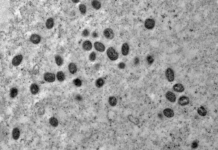

Equipe do Ministério da Saúde investiga cepa de mpox em SP

Profissionais, incluindo infectologista, avaliam o 1º caso da cepa 1b no país; paciente tem quadro estável

O Ministério da Saúde enviou uma equipe técnica a...